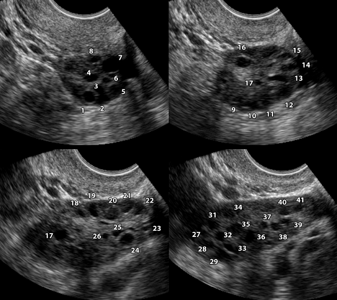

- множественные кисты яичников. Сонографически они могут выглядеть как «жемчужное ожерелье», скопление белёсых пузырьков или «косточки фрукта», рассеянные по всей ткани яичников;

- увеличение размеров яичников в 1,5–3 раза за счёт возникновения множества мелких кист;

Поликистоз яичников виден при ультразвуковом исследовании, хотя и не всегда. У 20% женщин (не прошедших ещё через менопаузу), не имеющих симптомов поликистоза как такового, при ультразвуковом исследовании обнаруживают поликистозные яичники.

УЗИ помогает выявить следующие признаки заболевания:

УЗИ органов малого таза позволяет выявить увеличенные яичники с многочисленными мелкими кистами.

СПКЯ обычно определяется как клинический синдром, вне зависимости от кистозных изменений яичников. Но присутствие в яичнике множества 2–6 мм или больших по размеру фолликулярных кист, содержащих атретичные клетки, является типичным. Яичники могут быть нормальных размеров или увеличены и иметь утолщенную и сглаженную белочную оболочку.

Более 10 фолликулов в каждом яичнике (выявленных при УЗИ тазовой полости), обычно раполагающихся по периферии и напоминающих нитку жемчуга